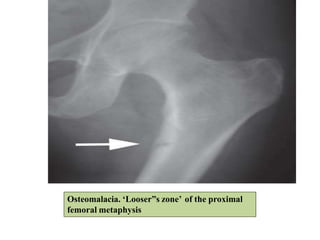

Common sites

Osteomalacia. ‘Looser”s zone’ of the proximal

femoral metaphysis